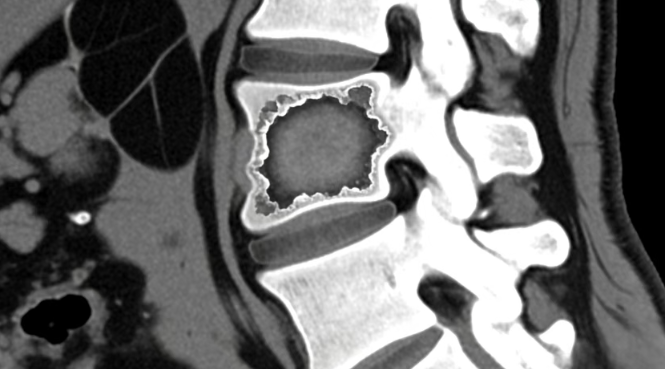

全腹增強CT檢查揭示兩項關鍵發(fā)現(xiàn):腰3、4椎體骨質被破壞,右側腰大肌形成巨大膿腫。結合影像結果及臨床癥狀,醫(yī)生最終確診為腰椎結核——結核菌破壞脊柱后,沿肌肉間隙蔓延形成“冷膿腫”,波及闌尾區(qū)域引發(fā)類似闌尾炎的腹痛。超聲率先捕捉膿腫線索,增強CT精準鎖定脊柱病灶,二者協(xié)同讓隱匿病灶無所遁形。